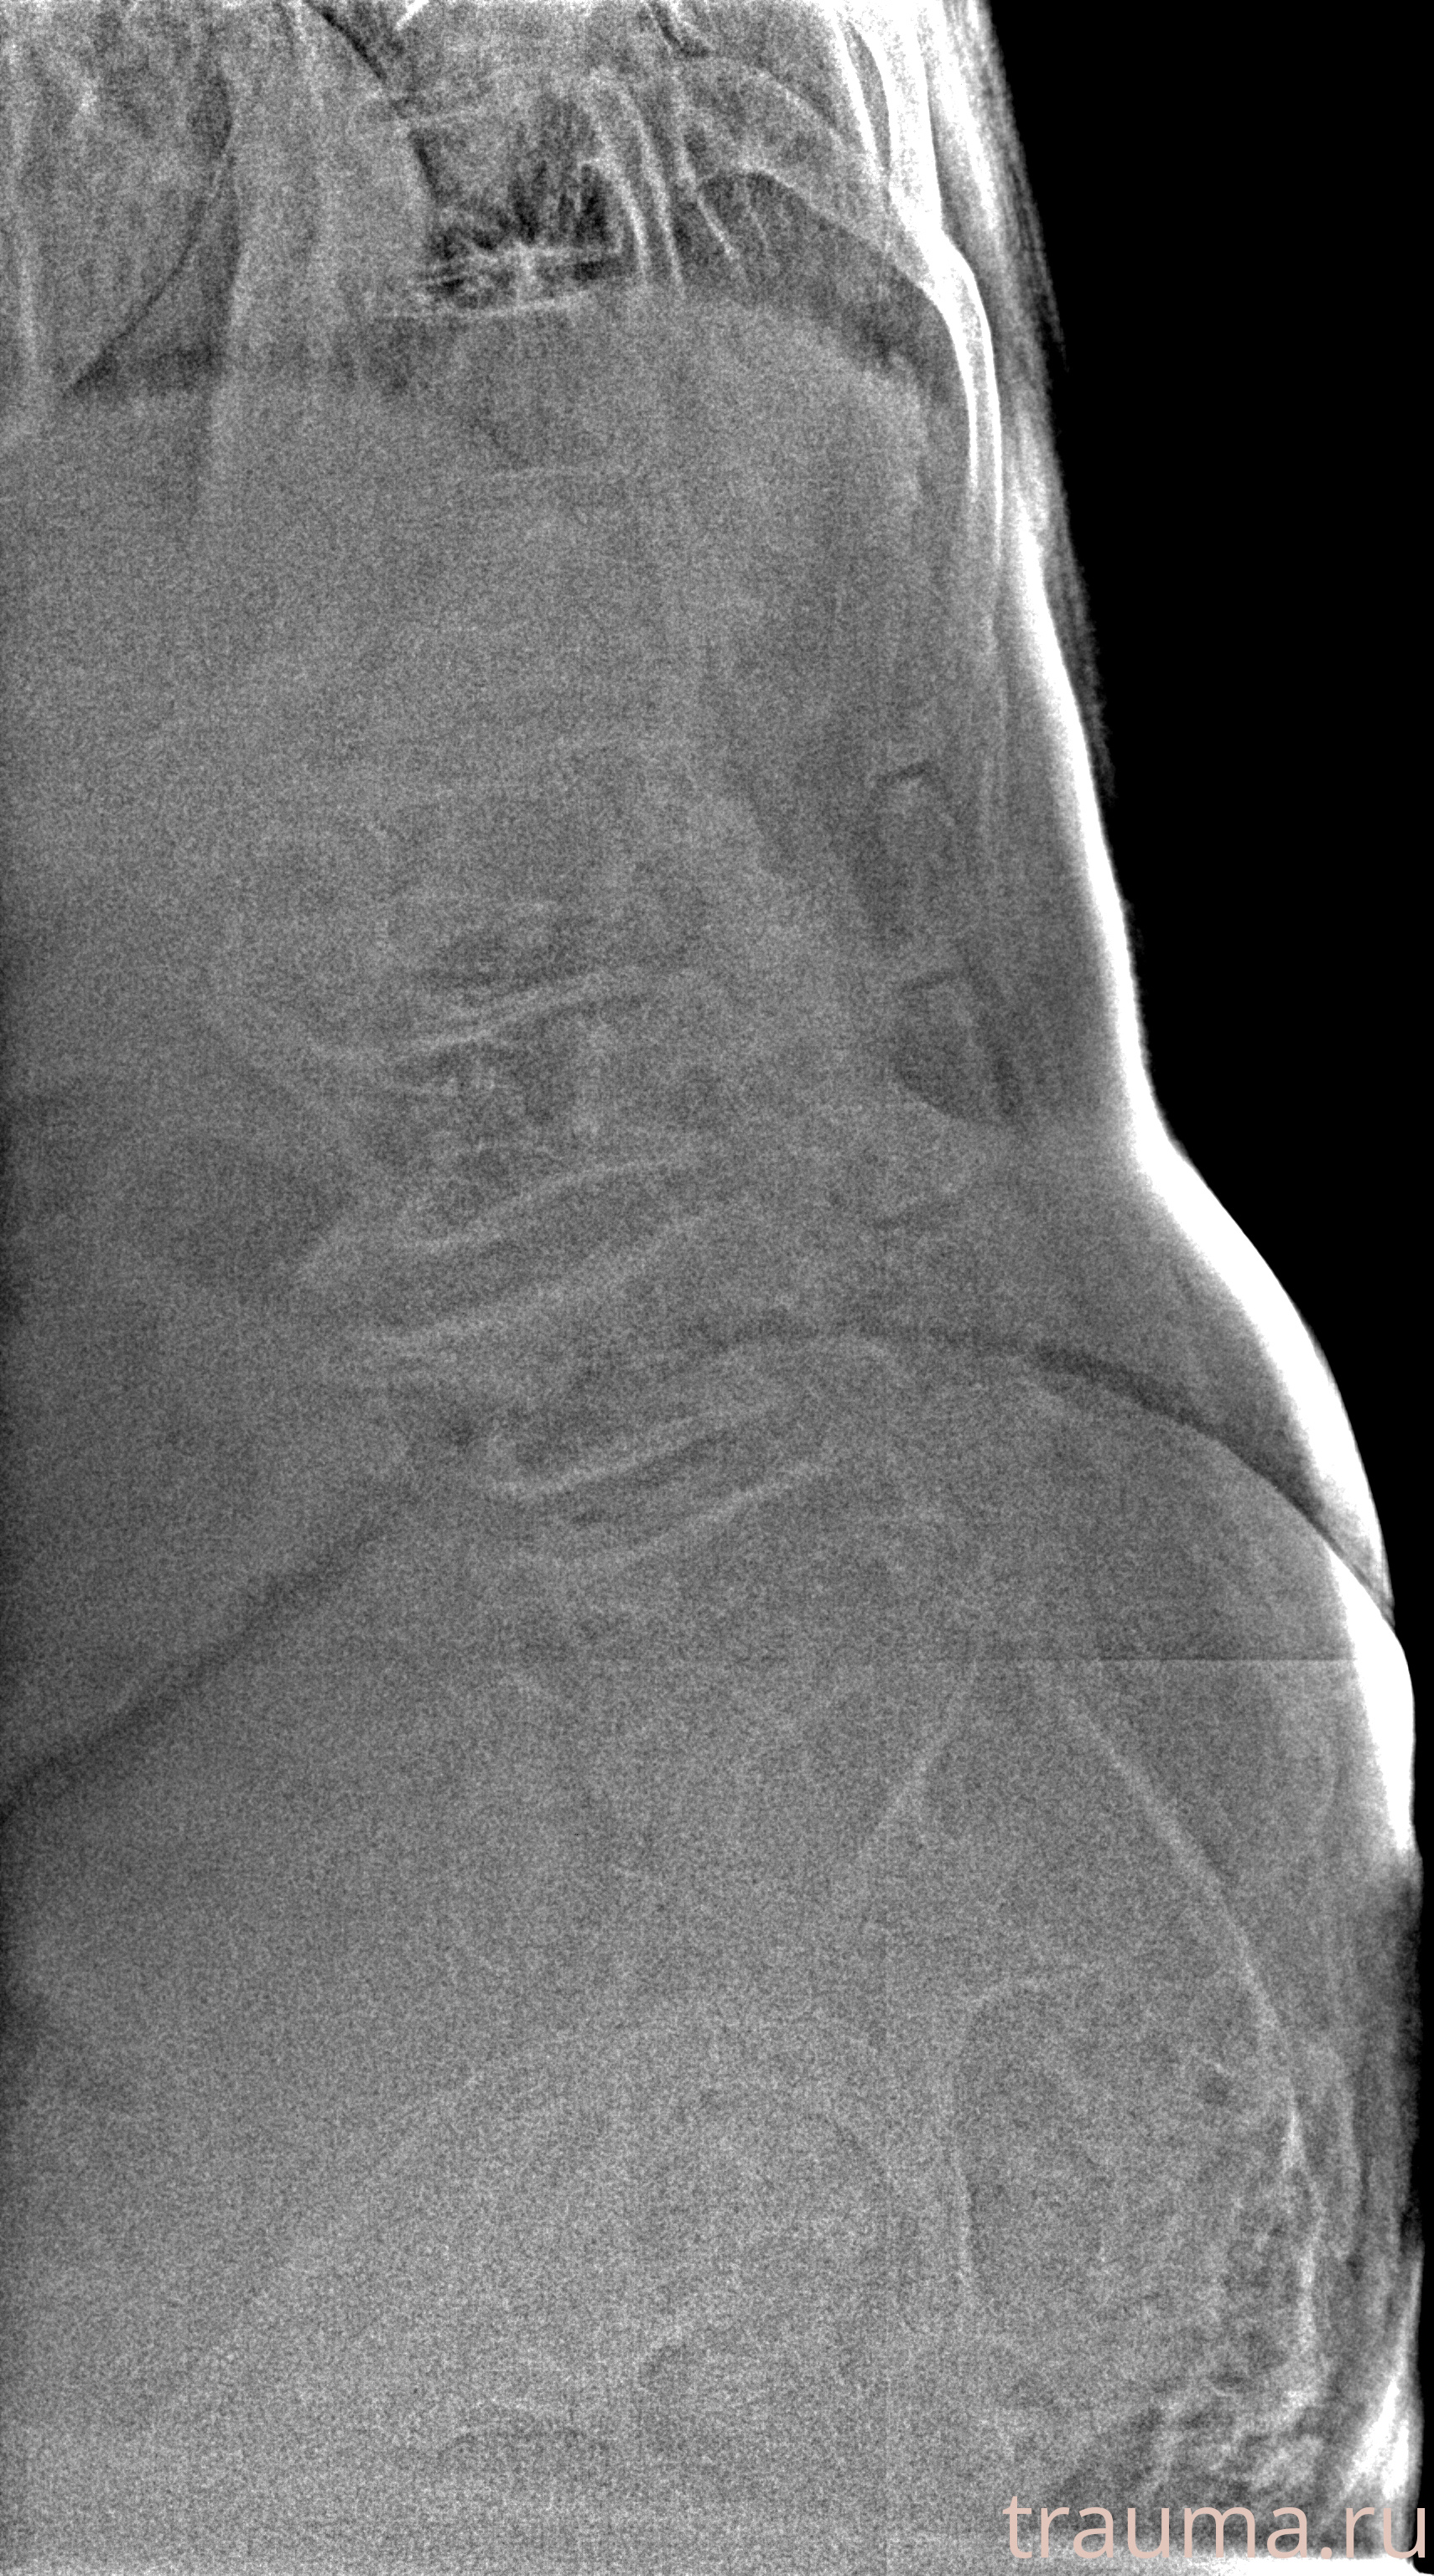

Рентген на дому: по вашему адресу приезжает врач-рентгенолог, травматолог-ортопед с мобильным рентгеновским аппаратом, проводит диагностику травмы или заболевания, делает необходимые рентгенограммы, дает рекомендации по дальнейшему лечению. Получить качественные снимки в домашних условиях возможно благодаря уникальной методике, разработанной МосРентген Центром для института  Склифосовского

при переломе шейки бедра и пневмонии от компании МосРентген Центр - партнера Института имени Склифосовского